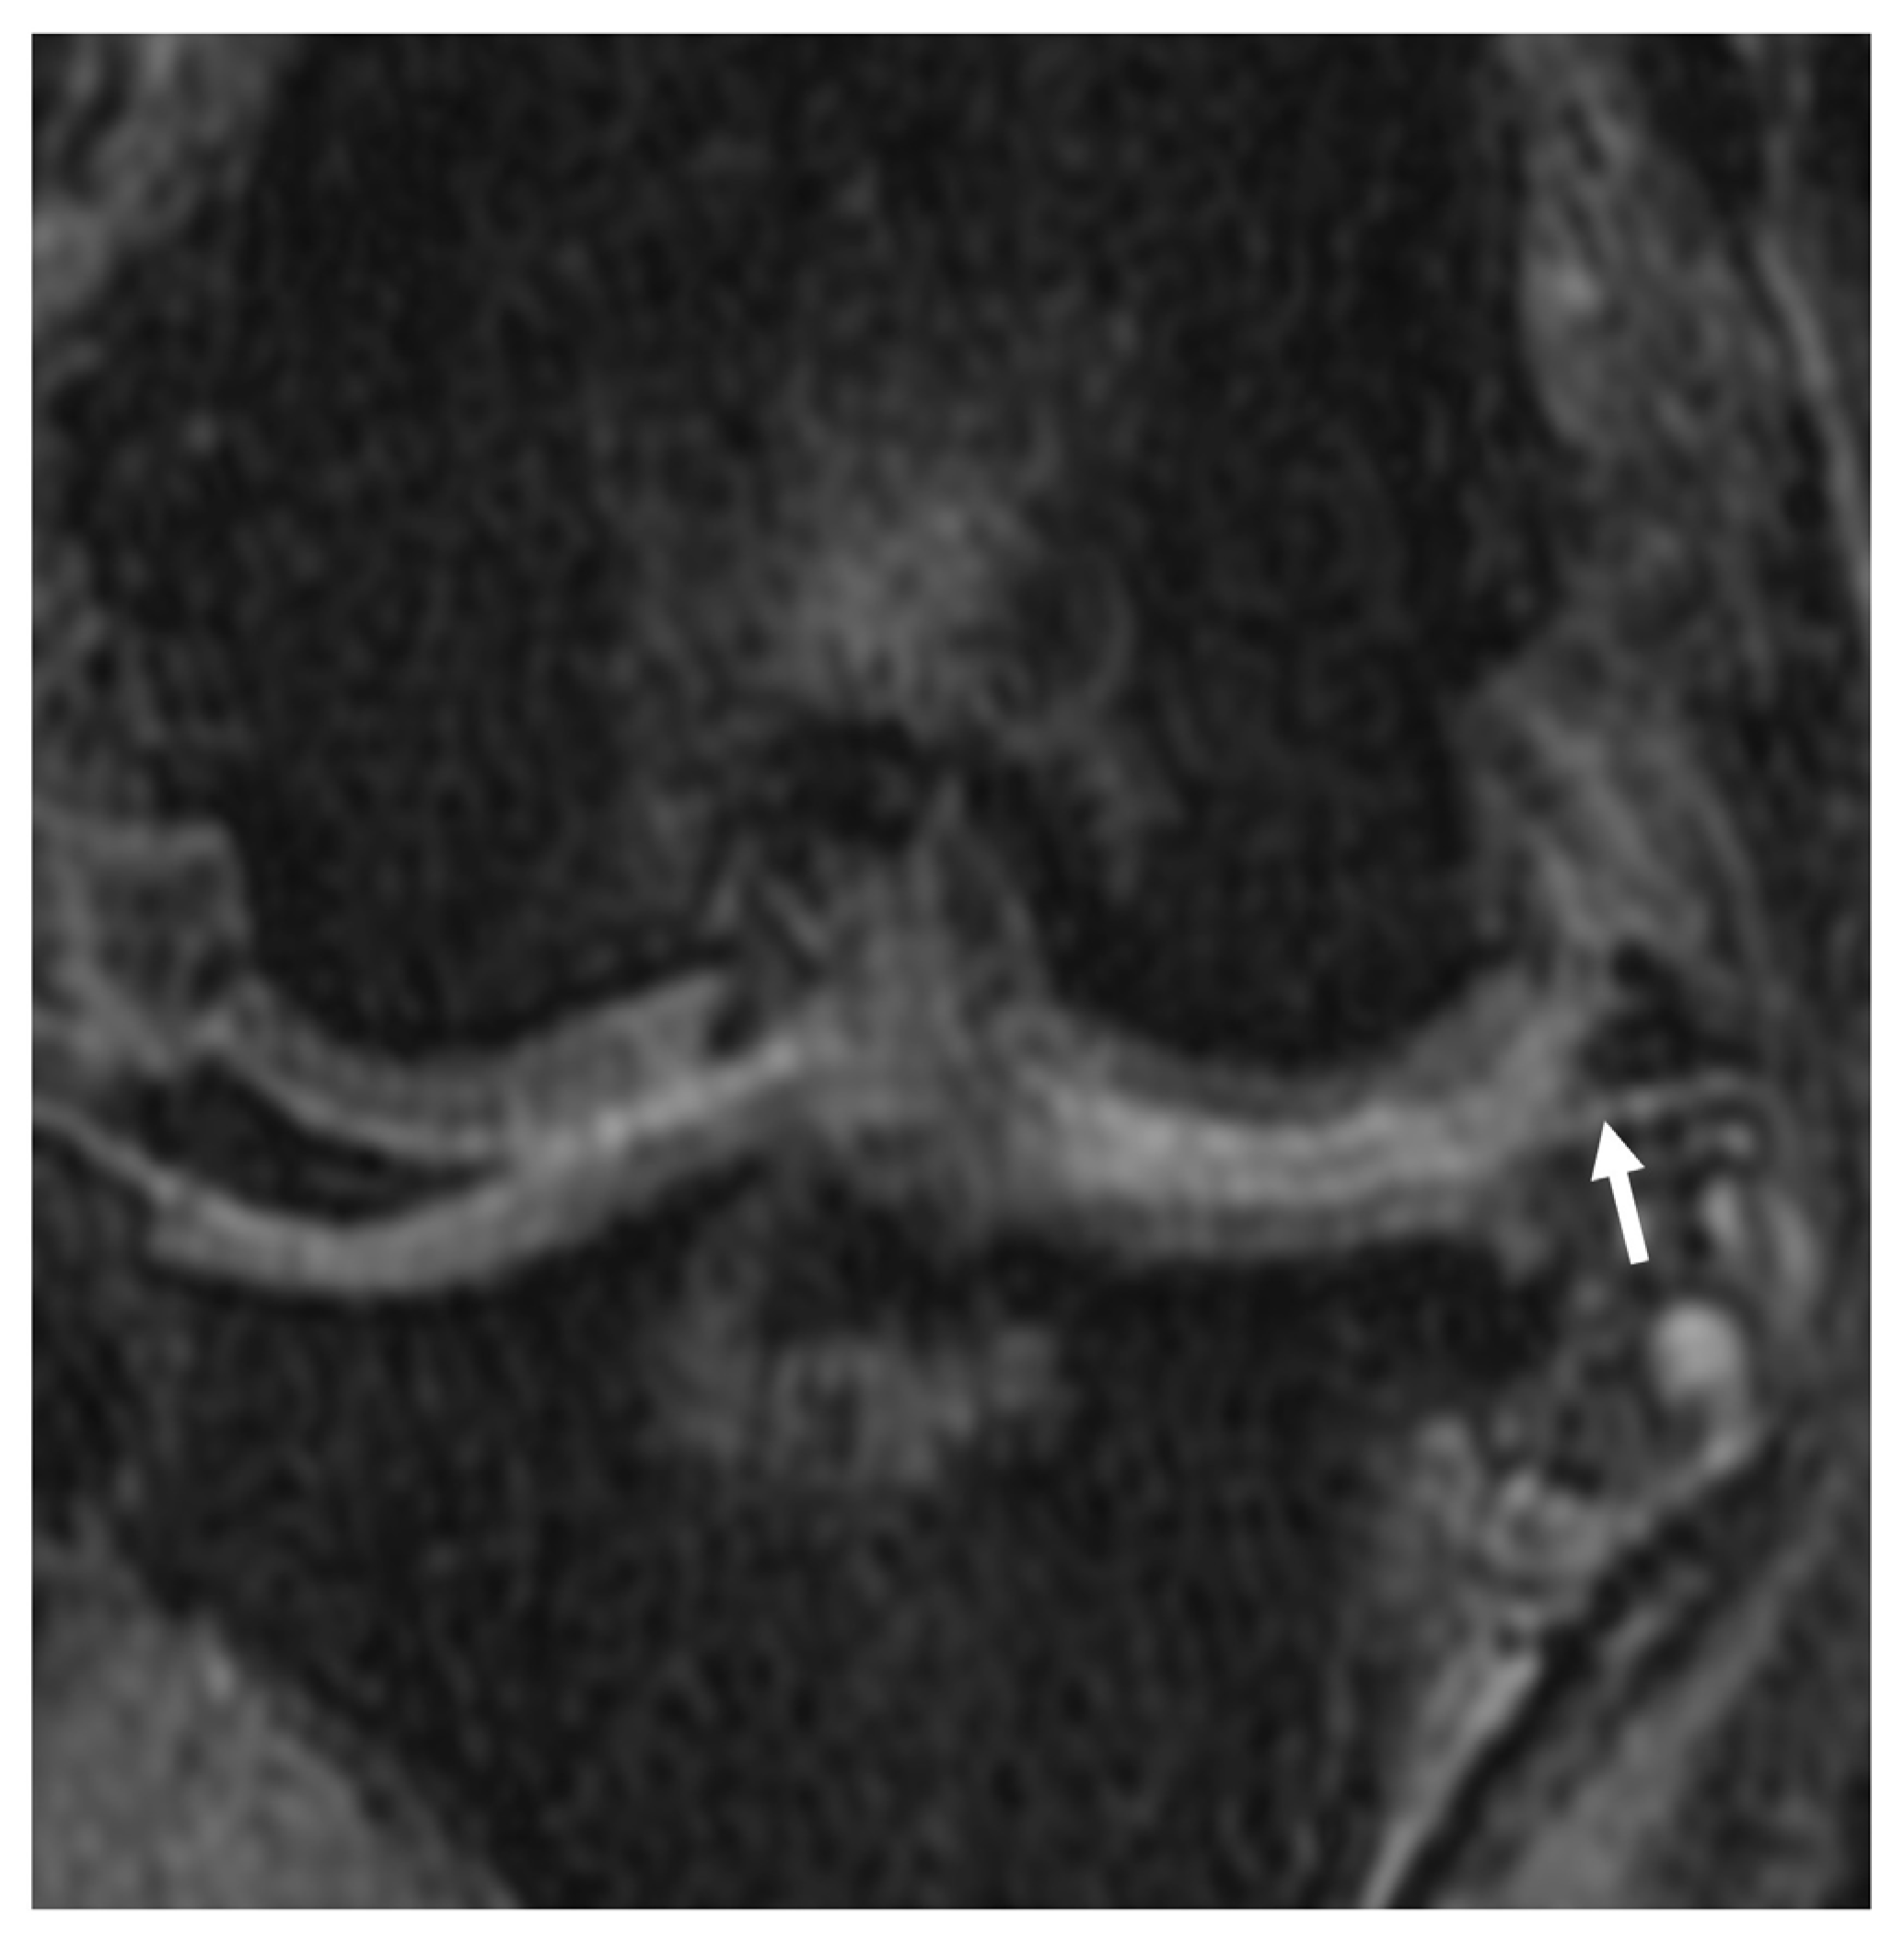

3.2.3. Synovial Effusion and Membrane Thickening

3.2.5. Meniscal and Cartilage Lesions